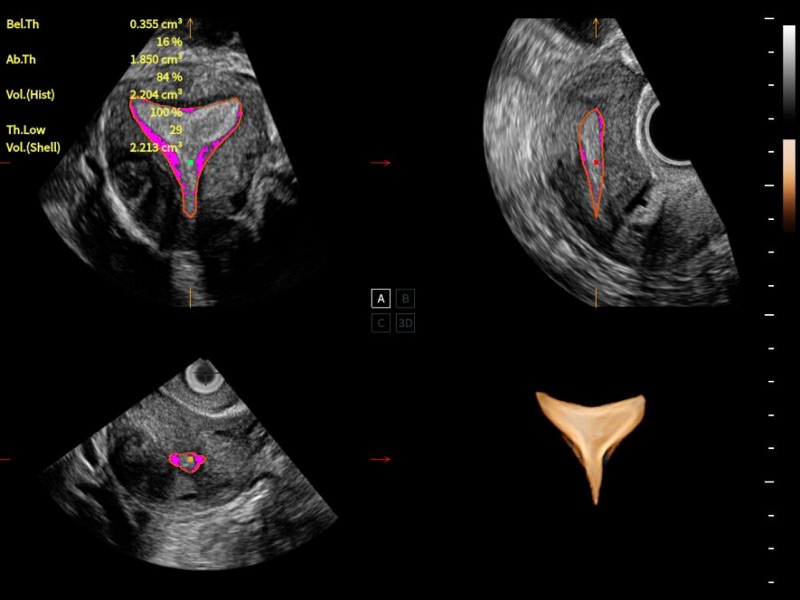

豐富的血流動(dòng)力學(xué)檢測(cè)技術(shù),可在不同醫(yī)療場(chǎng)景中高效捕捉血流信號(hào),助力臨床診療。

在傳統(tǒng)血流的基礎(chǔ)上優(yōu)化掃查和算法策略,能夠更好的抑制組織信息,提煉紅細(xì)胞運(yùn)動(dòng)信息,得到更高幀頻,高靈敏度和分辨率的血流信號(hào),還原更真實(shí)的血流動(dòng)力學(xué)。

通過(guò)光照模型,使二維血流顯示出立體的效果,增加血流的敏感性、成束性,減少外溢??梢院推渌煌难骷夹g(shù)聯(lián)合使用,融合不同技術(shù)的優(yōu)勢(shì)。輕松應(yīng)對(duì)微小血管,增強(qiáng)血流的立體效果,提升視覺(jué)敏感性。

通過(guò)創(chuàng)新的Matrix E自適應(yīng)濾波算法,能有效濾除軟組織和噪聲信號(hào),最大限度保留超低速微細(xì)血流的信號(hào);結(jié)合超長(zhǎng)時(shí)間域算法,極大提升細(xì)微血流的敏感性和空間分辨率,更真實(shí)的反應(yīng)組織、包塊的血流灌注情況。